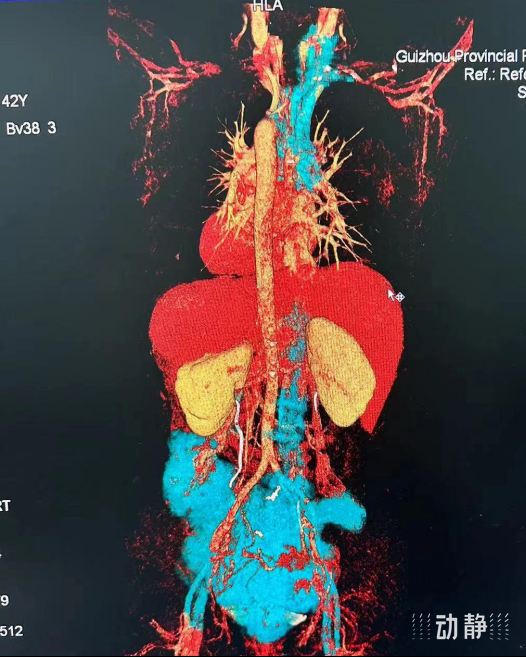

入院后,姚女士的多项影像学检查显示盆腔巨大子宫平滑肌瘤,并且伴随子宫深静脉-髂内外静脉-髂总静脉-下腔静脉直达右心房均可见瘤栓形成,甚至肺动脉中也有散在的瘤栓。原本长在盆腔的子宫肌瘤居然“跑”出了子宫,顺着静脉血管穿过腹腔和胸腔进入了心脏。在一次次心脏的收缩挤压作用下,姚女士心脏内的肿瘤随时可能嵌顿三尖瓣或断裂掉落,形成“瘤栓”导致肺栓塞,亦或本身存在的肺动脉瘤栓随时可能脱落,导致猝死。

省医妇科主任訾聃介绍,平滑肌瘤病虽是良性肿瘤,但姚女士体内的平滑肌瘤不仅体积巨大,而且存在侵犯周围器官及全身大血管的恶性肿瘤行为。若积极手术治疗,完整切除肿瘤,姚女士是完全有可能治愈的,但肿瘤累及多个重要器官以及静脉回流系统,手术风险极高。

12月21日,省医妇科联合心外科及血管甲状腺外科展开手术,在打开患者腹盆腔后,医生发现一个巨大的子宫多发肿瘤占据了整个盆腔,表面布满了怒张的血管,与周围的器官紧密粘连,肌瘤组织侵及膀胱和盆腔血管间隙。肿瘤还向卵巢静脉、子宫深静脉等重要血管延伸,形成了一条条肿瘤栓子,卵巢静脉、子宫静脉异常粗大。

多学科专家共同协作,历时8个多小时,成功切除了盆腔巨大子宫肌瘤原发病灶、心肺动脉瘤栓、下腔静脉及髂静脉瘤栓,患者体内的肿瘤被完全清除。术后患者转入ICU接受进一步监护,目前恢复良好。